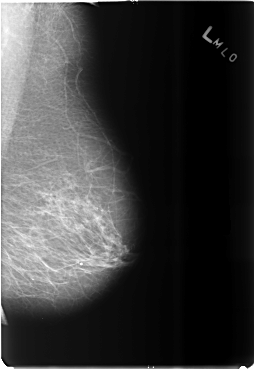

B_3489_1.LEFT_MLO

LEFT_MLO LINES 5896 PIXELS_PER_LINE 4064 BITS_PER_PIXEL 12 RESOLUTION 50 NON_OVERLAY